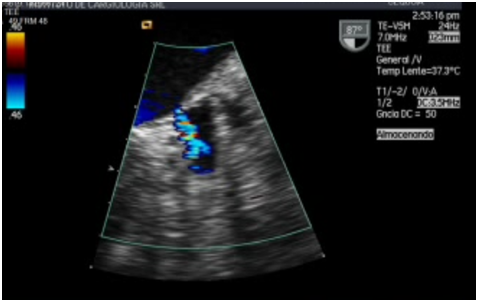

Figure 4 TEE in a projection located in the left atrial appendage using color doppler. The flow of filling of the left atrial appendage can be observed. The color doppler shows a high speed flow.